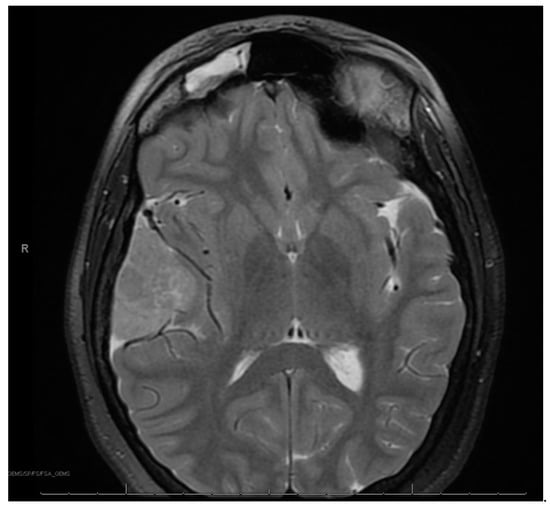

At age 12, brain MRI revealed that the intracranial meningioma and bilateral vestibular schwannomas were slightly larger. Spine MRI showed multiple thoracic and lumbar spine tumors, most significant at T4 and L2 and L4 cauda equina. There was also a possible ependymoma in the upper cervical spine, but there was no spinal cord compromise from any tumors. Surgery was again not indicated at that time. At age 13, face MRI revealed a large right frontotemporal meningioma that was considerably enlarged from the study three months prior, measuring approximately 5 × 3 × 5 cm compared to approximately 2.2 × 1 × 2.4 cm (Figure 2). There was mass effect of the surrounding brain structures, resulting in effacement of the right lateral ventricle and shift of midline by about 4 mm. She had worsening headaches and vomiting, prompting further imaging that revealed an increase in tumor size. This prompted a gross total resection via craniotomy of the right temporal meningioma. Pathology of the tumor confirmed an anaplastic meningioma of WHO grade III. Genetic testing on tumor demonstrated MLH1 loss of expression with focal positivity and retained expression of PMS2, MSH2 and MSH6. Due to the high-grade meningioma, she proceeded with radiation and completed 3600 Gy. Towards the end of the year, she returned to surgery to resect a nerve sheath tumor on the right side of the neck, with pathology confirming schwannoma.

Figure 2. Right frontotemporal anaplastic meningioma.